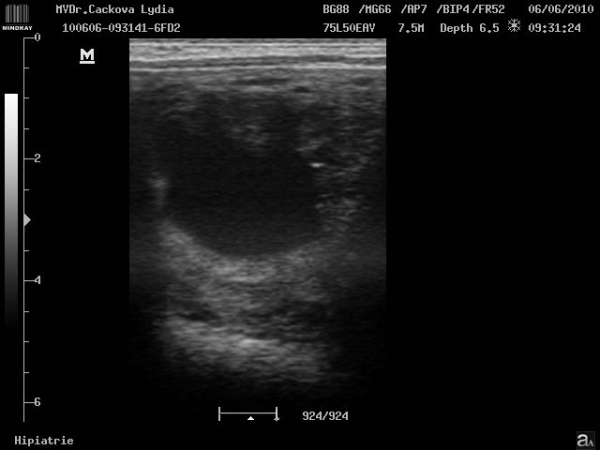

Preovulační folikul